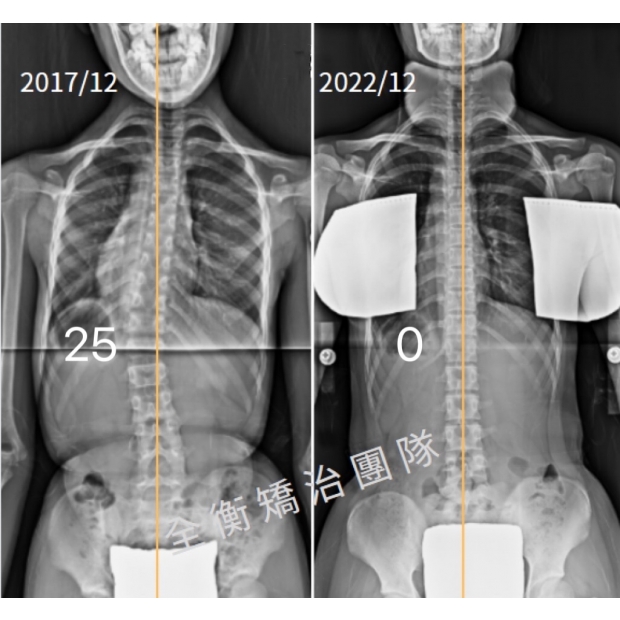

10嵗側彎女生,早期發現早期矯治的魔法:這也太直(值)了吧10嵗側彎女生,早期發現早期矯治的魔法:這也太直(值)了吧

國小四年級女生(10歲)發現脊椎側彎25度並開始積極治療,

經過5年的持續追蹤,目前已25度到0度,體態平衡也明顯回正 -